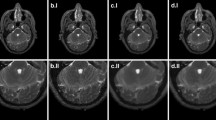

In this study we propose a novel correction scheme that filters Magnetic Resonance Images data, by using a modified Linear Minimum Mean Square Error (LMMSE) estimator which takes into account the joint information of the local features. A closed-form analytical solution for our estimator is presented and it proves to make the filtering process far simpler and faster than other estimation techniques that rely on iterative optimization scheme and require multiple data samples. An experimental validation of our correction scheme was carried out through large scale experiments using both clinical and synthetic MR images, artificially corrupted with rician noise of σ varying from 1 to 40. These noisy images were filtered using our proposed method against the classical LMMSE, the Non-Local Means filter and the Nonlocality-Reinforced Convolutional Neural Networks (NRCNN) techniques. The results show an outstanding performance of our proposed method, given the fact that from σ ≈ 12 onwards, the proposed method outperforms all other methods. Another attention-grabbing feature of our method is that its Structural Similarity does not vary sharply [0.87, 0.95] across the σ spectrum as the other three techniques, which implies that this method can work on a wider range of deteriorated images than the rest of the techniques.